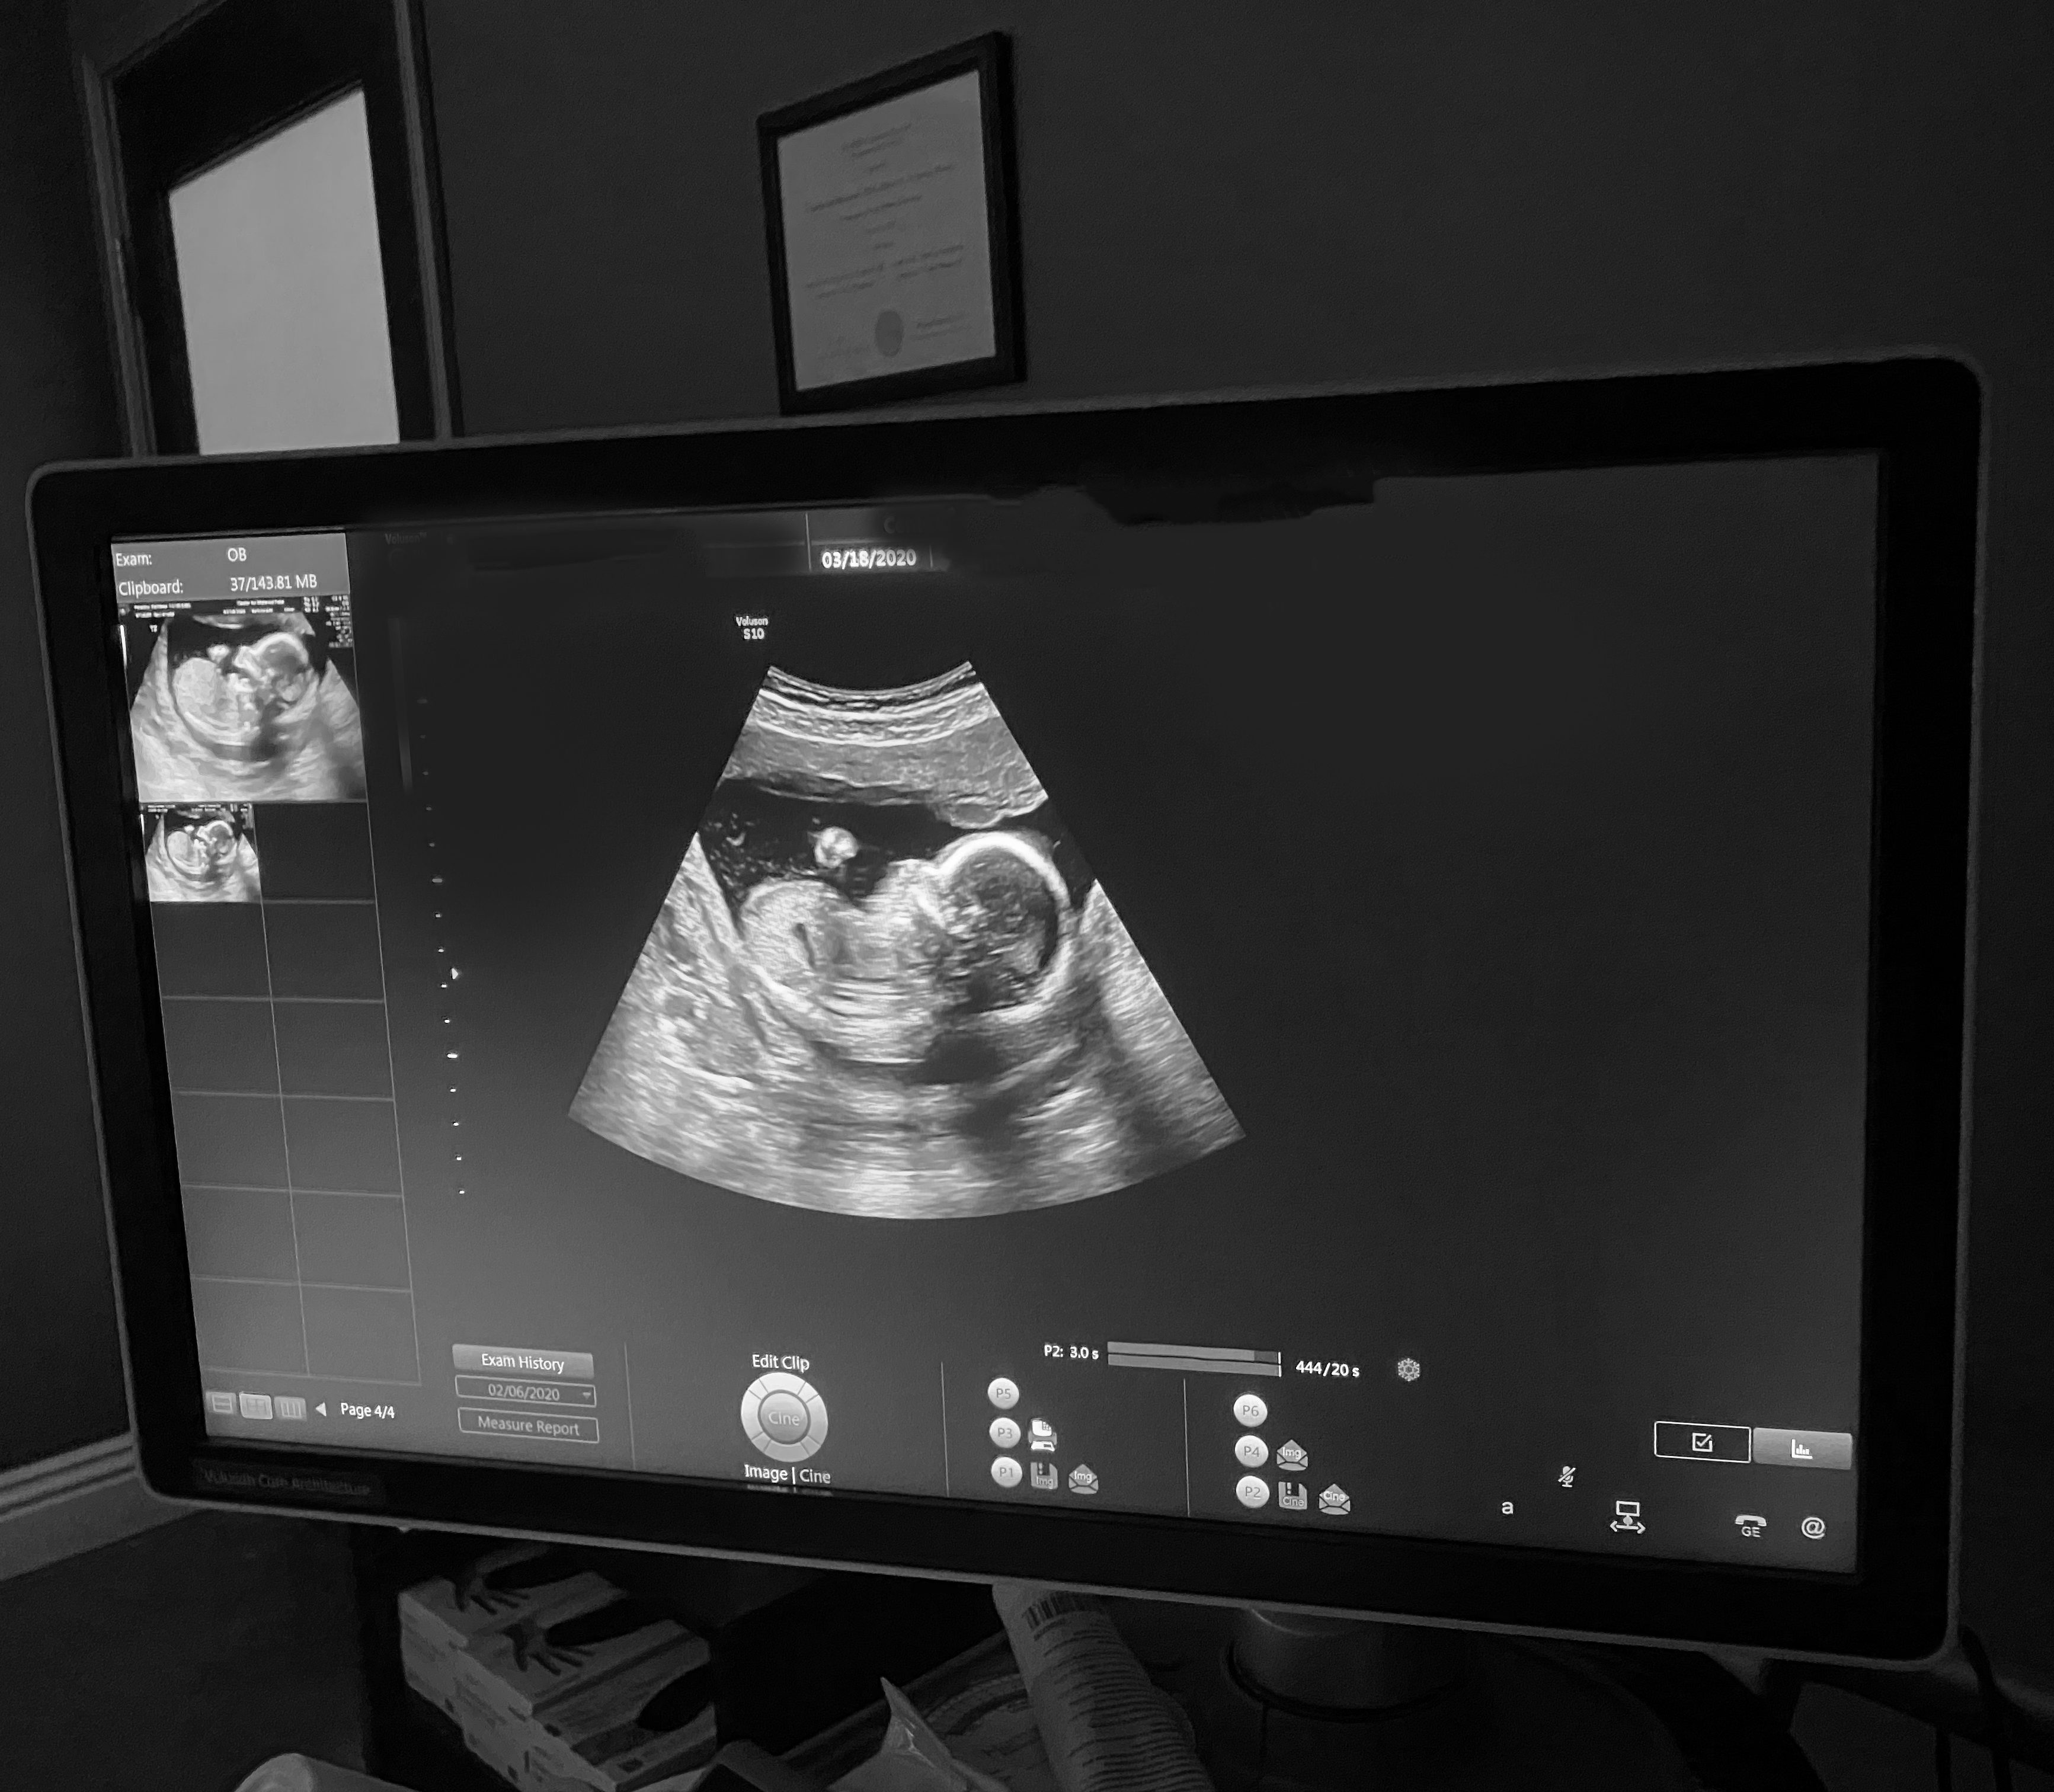

December 2019. That faint little second line that I saw on my early result pregnancy test, five days after my FET (frozen embryo transfer), wasn’t kidding. It got darker and darker as the days passed. And all of the sudden, I’m like any other pregnant lady -- headfirst into my first trimester, barely able to eat from nausea, taking two harcore naps a day and sobbing over animal rescue videos and sappy movies - even more than usual. Pregnancy hit me hard and fast. Though I felt like complete crap, I was so stinking happy.

The FET. No pain. You just lay there and watch on the big screen as they bring your thawed embryo into the room and finally give it a home. Then you lay there for about fifteen minutes, alone, trying to mentally will your baby to stick, aka not fall out or get lost or whatever else could go wrong up there.

Then you get dressed, go home and wait. And hope.